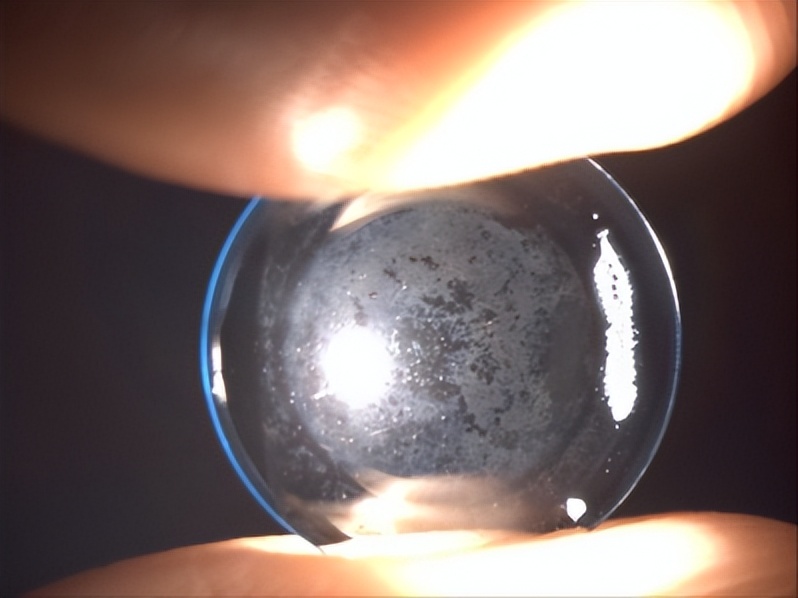

泪液中含有多种蛋白质,并且多数带有负电荷。由于角膜塑形镜的材料多为氟硅丙烯酸酯等带有正电荷的高分子聚合物,如长期使用不含蛋白酶的多功能护理液,或者镜片未定期行去蛋白处理,就会形成镜片蛋白沉淀。镜片内表面的“凹槽”如RC和激光标记处最容易发生蛋白沉淀(图12),但也可发生在整个镜片内表面(图13)。一旦镜片表面形成结晶状的蛋白沉淀,不仅难以被去除,而且会对角膜上皮造成机械性损伤(图14),此时需要积极更换镜片。

图13. 蛋白沉淀于镜片后表面